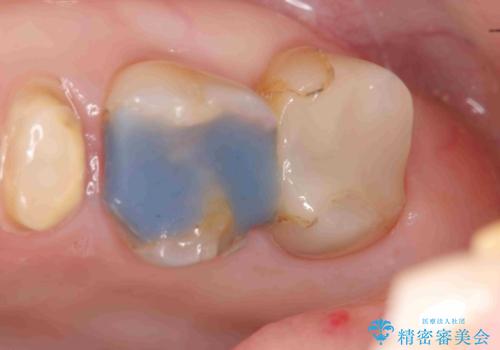

放置してしまった深い虫歯の治療

- 虫歯治療を中断し放置、痛みが出てきたため当院を初診来院されました。

虫歯の深化により根管治療、歯周外科手術を行い歯肉の状態を改善し精密なセラミッククラウンを製作する治療を計画します。